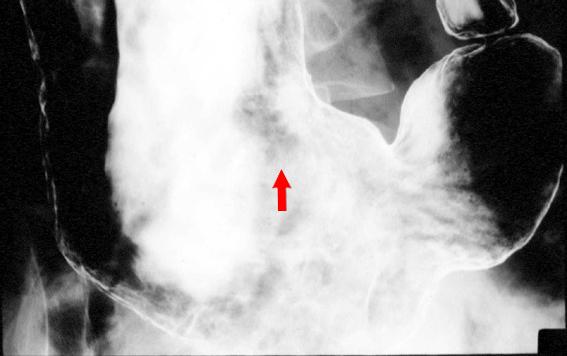

胃悪性リンパ腫のX線像  腹臥位による胃の前壁造影です。胃体下部の前壁に、均一にバリウムのたまる浅い陥凹がみられます(矢印)。

疾患(病理主体)の分類悪性リンパ系腫瘍/MLP型悪性リンパ腫

部位(臓器別)胃(部位)/体部

病変の最大径(ミリ)20〜24